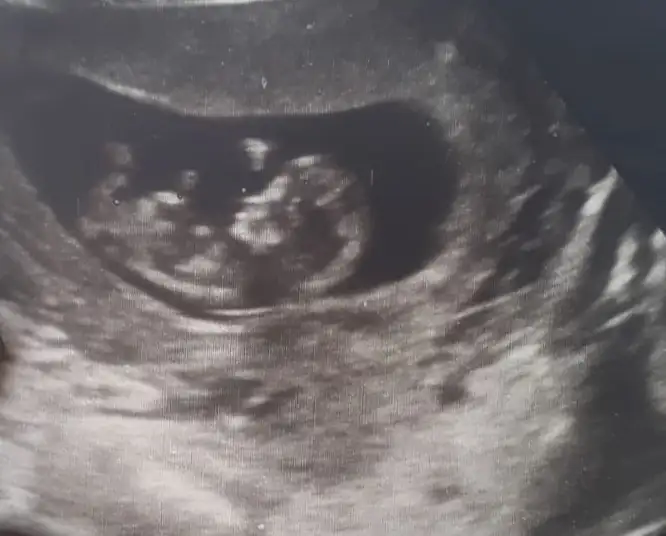

Bence kıza benziyoEki Görüntüle 2543768

Benim attığım resmede bakabilirmisin canımBence kıza benziyo

Tsk ederm ❤Bence kıza benziyo